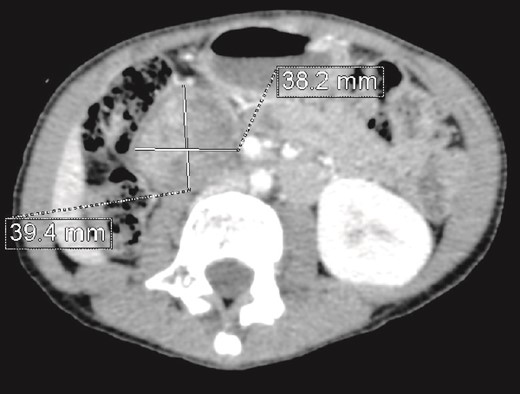

We present the case of an 8-year-old boy with no significant medical history and no prenatal diagnosis of congenital renal malformation. During a physical examination following a minor abdominal injury sustained while playing, a right flank abdominal mass was discovered. Clinically, the patient’s general condition was stable. The mass was non-tender, firm, and fixed to deep planes while mobile over superficial planes. There was no evidence of varicocele. Abdominal ultrasonography and computed tomography (CT) revealed a well-circumscribed, well-encapsulated solid mass measuring 9 × 6 cm, with areas of necrosis. The mass was located in the right kidney, in contact with the cephalic portion of the pancreas and closely abutting the inferior vena cava, which was displaced to the left. The right kidney was not visualized, and no secondary lesions were detected (Fig. 1). Magnetic resonance imaging (MRI) was performed to further characterize the tumor’s origin. However, it confirmed only the presence of the tumor and the absence of normal renal parenchyma, providing no additional information regarding the origin of the upper right abdominal quadrant mass (Fig. 2). Given the unclear origin of the tumor, a CT-guided biopsy was performed. Pathological analysis of the biopsy revealed nephroblastoma without signs of anaplasia. The patient was subsequently treated with neoadjuvant chemotherapy, consisting of vincristine and actinomycin D for 4 weeks, following the SIOP 2001 protocol, and was scheduled for nephrectomy. Post-chemotherapy CT evaluation demonstrated a 75% reduction in the size of the right kidney mass (Fig. 3). The patient underwent an open nephrectomy. Intraoperatively, an atretic ureter was identified, with no visible normal renal parenchyma. An extended right nephrectomy was performed (Fig. 4a and b).

CT scan evaluation after chemotherapy: Regression in size of the right kidney mass with an estimated response of 75%.